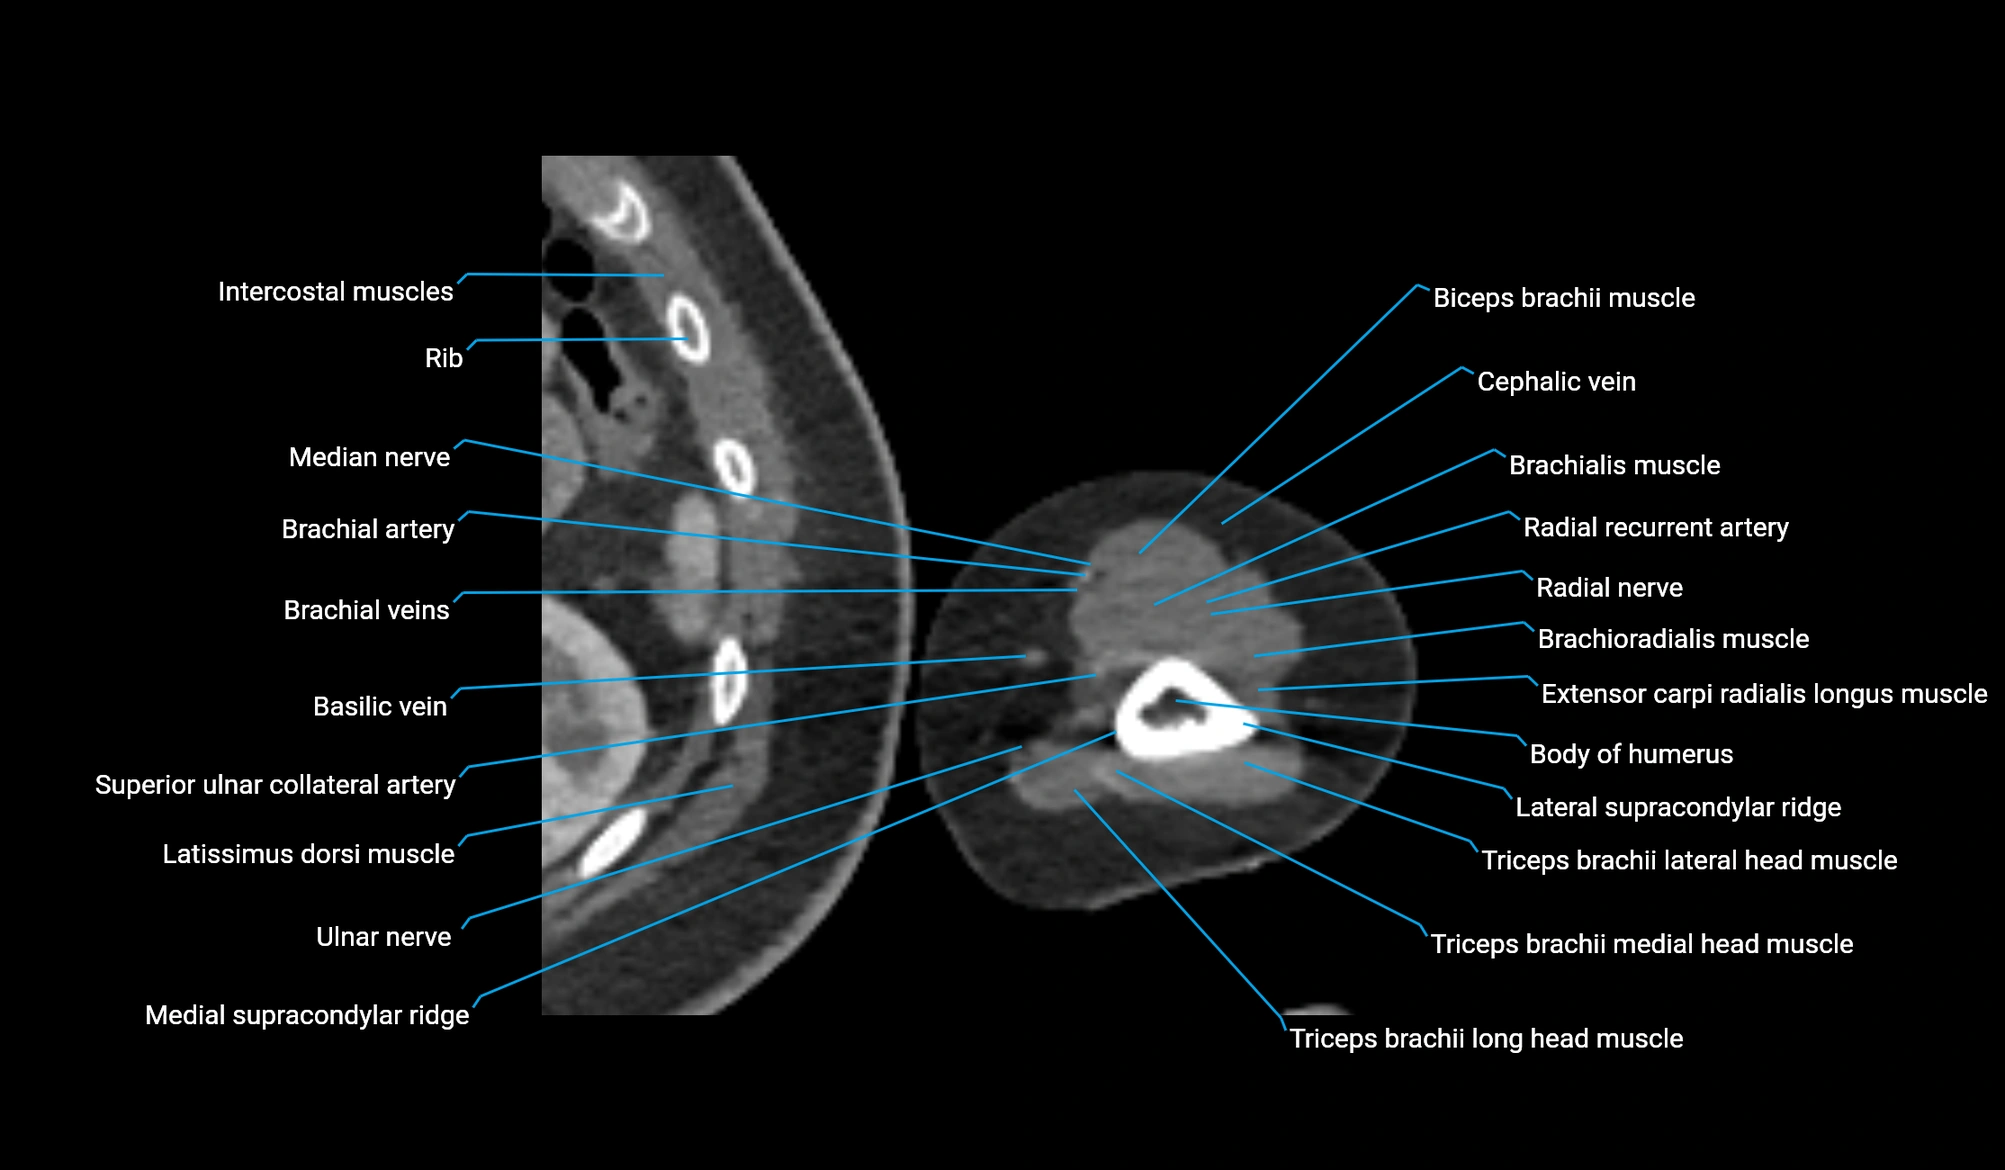

CT image